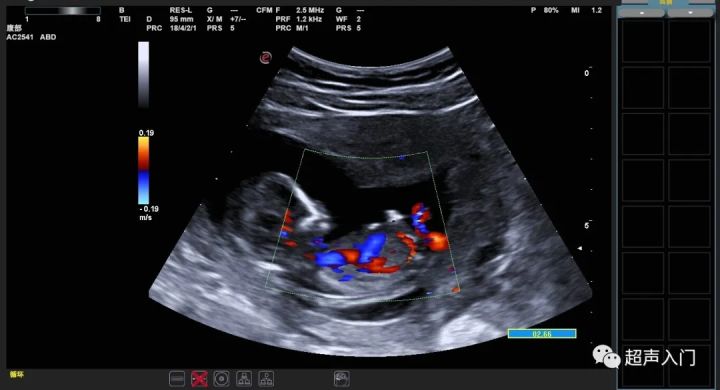

值得注意的是:NT增厚与自然流产、胎儿畸形有关,此时胎儿并无染色体异常。此外,早孕期及中孕早期NT厚度大于正常,出现严重心脏畸形者占56%,胎儿可出现早期心衰,静脉导管出现异常血流信号,并与双胎输血征中的受血儿、珠蛋白生成障碍性贫血纯合子胎儿等有关,是发现上述疾病的重要线索。